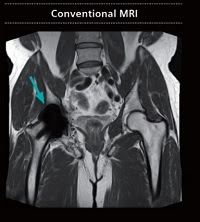

左:従来の MRI による金属インプラント画像

右:High-V MRI による金属インプラント画像